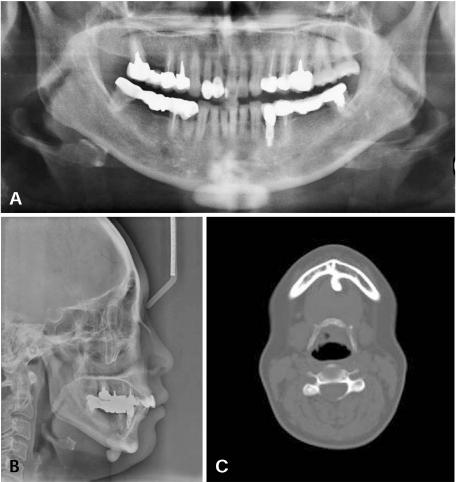

颅面部骨瘤

Osteomas of the craniofacial region.

A retrospective study of 18 patients diagnosed with osteomas in the craniofacial region was performed. The age, gender, location, symptoms, and the radiological findings were recorded.

RESULTS

There were 13 women and 5 men from 18 years to 69 years of age (mean age, 42±27 years). Fourteen osteomas were found in the mandible (78%), two in frontal sinus, one in sphenoid bone, and one in maxilla.

结果

18例患者中,女性13例,男性5例,年龄18岁至69岁(平均年龄42±27岁)。14例骨瘤位于下颌骨(78%),2例位于额窦,1例位于蝶骨,1例位于上颌骨。